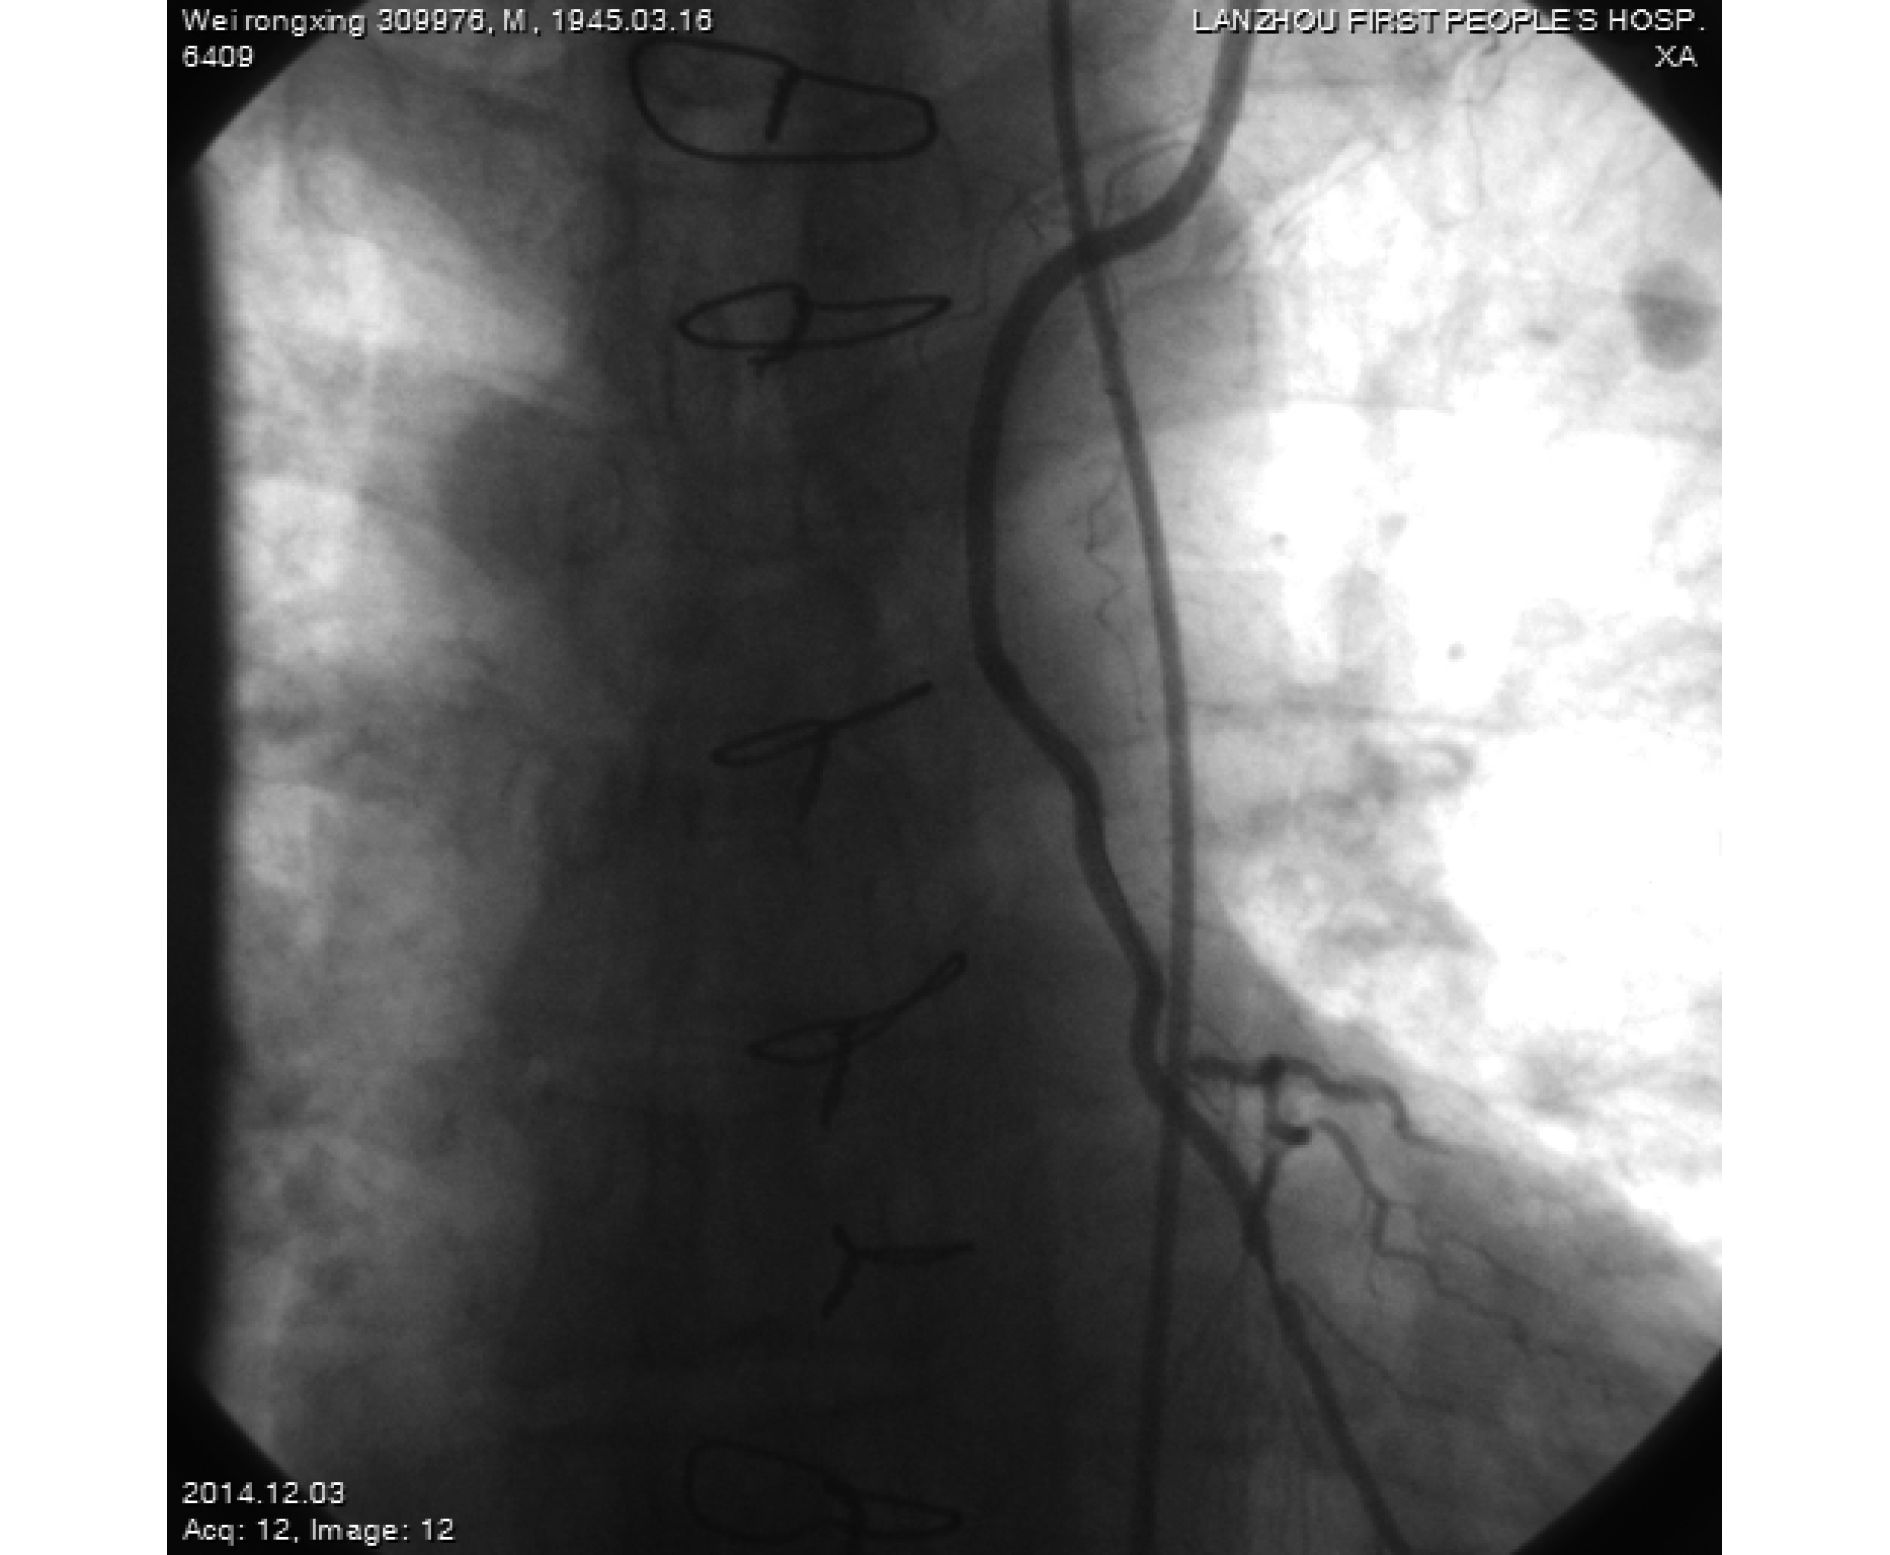

臨床資料 患者,男,69 歲,主因“冠狀動脈旁路移植術后 3 年,再次發作胸悶、氣短、乏力不適 1 月”就診。既往高血壓 3 級及 2 型糖尿病病史。3 年前冠狀動脈旁路移植術移植血管為左乳內動脈-左前降支(LIMA-LAD)、升主動脈(aorta ascendens,AO)-大隱靜脈(saphenous vein graft,SVG)-后降支(posterior descending artery,PDA)。術后常規服用阿司匹林、氯吡格雷等藥物。入院體格檢查未見明顯異常。心電圖提示:陳舊性下壁心肌梗死。考慮冠狀動脈橋血管、其他冠狀動脈血管閉塞可能。左側橈動脈行冠狀動脈造影檢查示:左冠前降支閉塞,回旋支(left circumflex artery,LCX)中斷可見 95% 左右狹窄,前向心肌梗死溶栓試驗(TIMI)血流 2 級;右冠近、中段彌漫性病變,最狹窄處 90%,前向 TIMI 血流 1 級,橋血管 LIMA-LAD 通暢,可見吻合口遠端近吻合口處 99% 狹窄(圖 1);尋找 AO-SVG-PDA 靜脈橋血管開口失敗,但可見 PDA 至橋血管逆灌通暢,結合入院 CTA 結果(AO-SVG-PDA 橋血管通暢),判斷靜脈橋血管通暢。